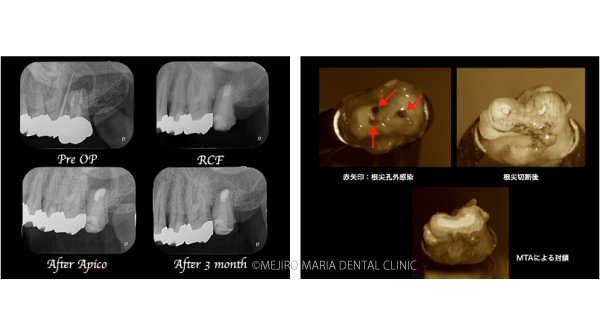

【症例】抜歯を宣告された歯を外科的根管治療「歯根端切除術」で保存(1年後経過観察追加)